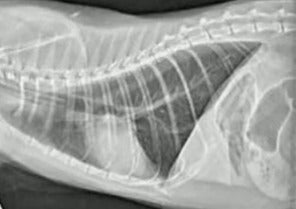

Diagnostic Imaging Challenges - Common Pitfalls and How to Avoid Them

This session will cover what to do when initial empiric treatment fails. We will discuss further investigation and treatment options of a rabbit with respiratory disease and a guinea pig with cystitis, focusing on what is realistic in general practice.

Radiology

Presented by Pete Mantis, DVM, DipECVDI, FHEA, MRCVS